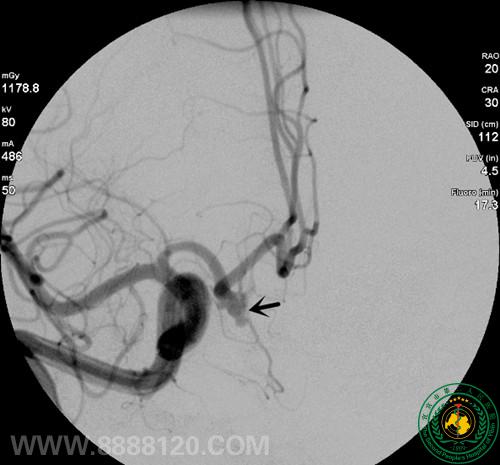

我科成功完成1例复杂前交通动脉瘤的介入治疗

我科成功完成1例复杂前交通动脉瘤的介入治疗9453